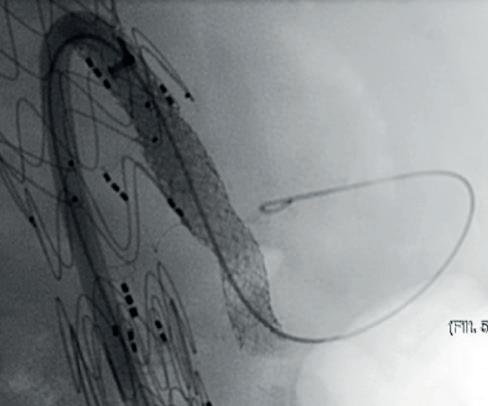

Fiber Optic RealShape (FORS) technology from Philips also shows potential in this space, offering the benefits of 3D navigation, unlimited viewing angles, and the radiation-reducing benefits associated with the use of light instead of fluoroscopy, Van Herwaarden highlighted. He noted that one drawback is the fact there are only a limited number of devices available.

Finally, the presenter gave an overview of the pros and cons of image fusion. He stated that there is one system in this space—the Cydar Medical system—that offers automated registration. This technology compares the anatomy visible on live fluoroscopy with anatomy of a preoperative computed tomography angiography

(CTA) and automatically produces 3D overlay, he explained. According to the presenter, this technology offers “a significant reduction of contrast agent and also reduction of procedure time,” despite having a somewhat “complex setup”. Image fusion is “widely available” and, in the presenter’s opinion, “should be used in all complex procedures”.

Van Herwaarden summarised that these technologies show radiation-reducing potential, the small number of available publications suggest that these techniques are “still minimally applied”. According to the presenter, the future of these technologies lies in their combined use. For example, he said that, while electromagnetic tracking and FORS are “still under development,” they do offer “an even greater promise for simplifying complex procedures and realising dose reduction for patients and for staff,” when used in combination with IVUS or a robotic navigation system.